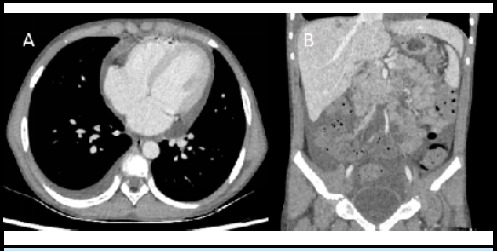

伴有呼吸窘迫和多器官受累的高嗜酸性粒细胞综合征在儿童中并不常见。必须根据临床、实验室和影像学特征来识别这种病症。应尽早使用皮质类固醇,以稳定患者病情并防止器官受损。热带感染是儿童常见的继发性病因,因此需要服用地西泮。我们介绍了一例呼吸窘迫、嗜酸性粒细胞明显增多、器官涉及肺部(肺部浸润伴积液)、心脏(心包积液)和腹部(腹水伴肝脏浸润)的青少年男性病例,该病例通过使用类固醇和抗蠕虫药得到了控制。该病例强调了识别嗜酸性粒细胞过多综合征患者、进行全面评估和开始治疗的重要性。

Hypereosinophilic syndrome with respiratory distress and multiorgan involvement is not so common in children. It is essential to identify this entity based on clinical, laboratory, and imaging features. Corticosteroids should be instituted at the earliest to stabilize the patient and prevent organ damage. Tropical infections are a common secondary cause in children warranting the administration of Diethylcarbamazine. We present a case of an adolescent male in respiratory distress with marked eosinophilia and organs involving the lungs (pulmonary infiltrates with effusion), heart (pericardial effusion), and abdomen (ascites with infiltrates in the liver) which was managed with steroids and anthelmintics. The case highlights the importance of identifying patients with Hypereosinophilic syndrome in pursuing thorough evaluation and commencing therapy.